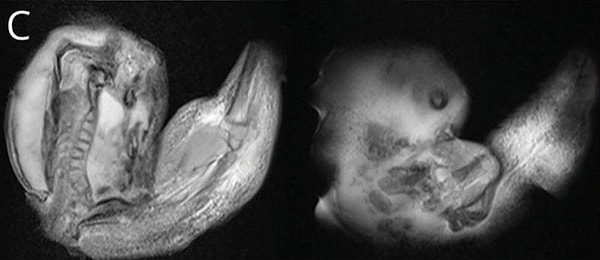

Как только МРТ показала существование близнеца, который давил на ее мозг, врачи поняли, что плод нужно немедленно удалить. К тому времени, как они смогли извлечь его, близнец уже несколько месяцев рос внутри черепа малышки — у него развились кости, органы и конечности.

Доктора рассказали, что у каждого брата и сестры было «множество хорошо развитых органов», включая нервную, пищеварительную и дыхательную системы. Все они были связаны с родным братом единственной артерией и веной, которые, по словам врачей, когда-то были пуповиной.